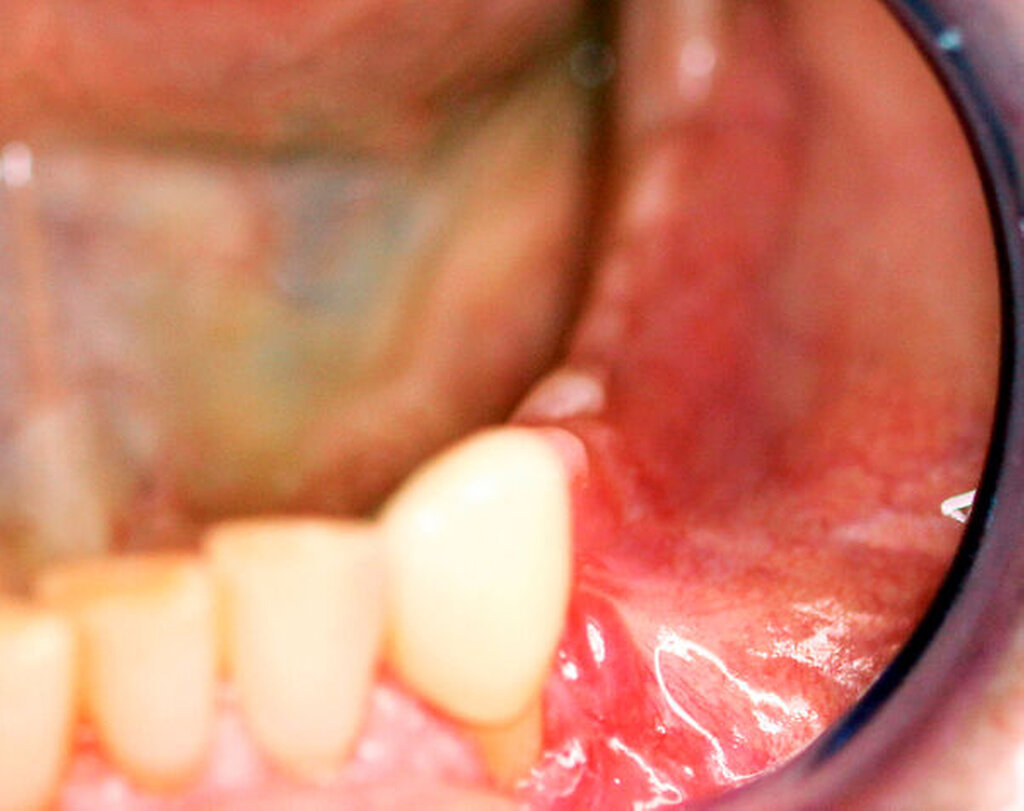

Nach der Entfernung des Wurzelrests 44 wurde der Nervus mentalis am Foramen mentale dargestellt und aus dem umgebenden Weichgewebe frei präpariert (Abbildung 6). Aus der Resektionshöhle und nach Entfernung der vestibulären Knochenlamelle auch aus dem Unterkieferkörper konnte anschließend der Sealer samt der extrem weichen Spongiosa entfernt werden. Die Lage der radiologisch dichten Verschattung im krestalen Bereich regio 36 konnte ebenfalls lokalisiert und problemlos entfernt werden. Bei dem Fremdkörper handelte es sich vermutlich um einen Amalgamrest (Abbildung 7).

Da der Sealer auch entlang des Mandibularkanals nach dorsal überpresst war, wurde zunächst eine Nervlateralisation mittels Piezosurgery durchgeführt. Nach vollständiger Freilegung des Nervs konnte der Sealer nahezu vollständig aus dem Kanal geborgen werden (Abbildung 8).

In der postoperativen DVT-Aufnahme zeigt sich weiterhin Sealer randständig an der mesialen Alveolenwand des Zahnes 34. Wir entschieden uns für das Belassen des Materials, da die vollständige Entfernung zum Verlust der distalen Alveolenwand geführt hätte und damit auch zum Verlust des Zahnes 33 (Abbildungen 9 und 10).